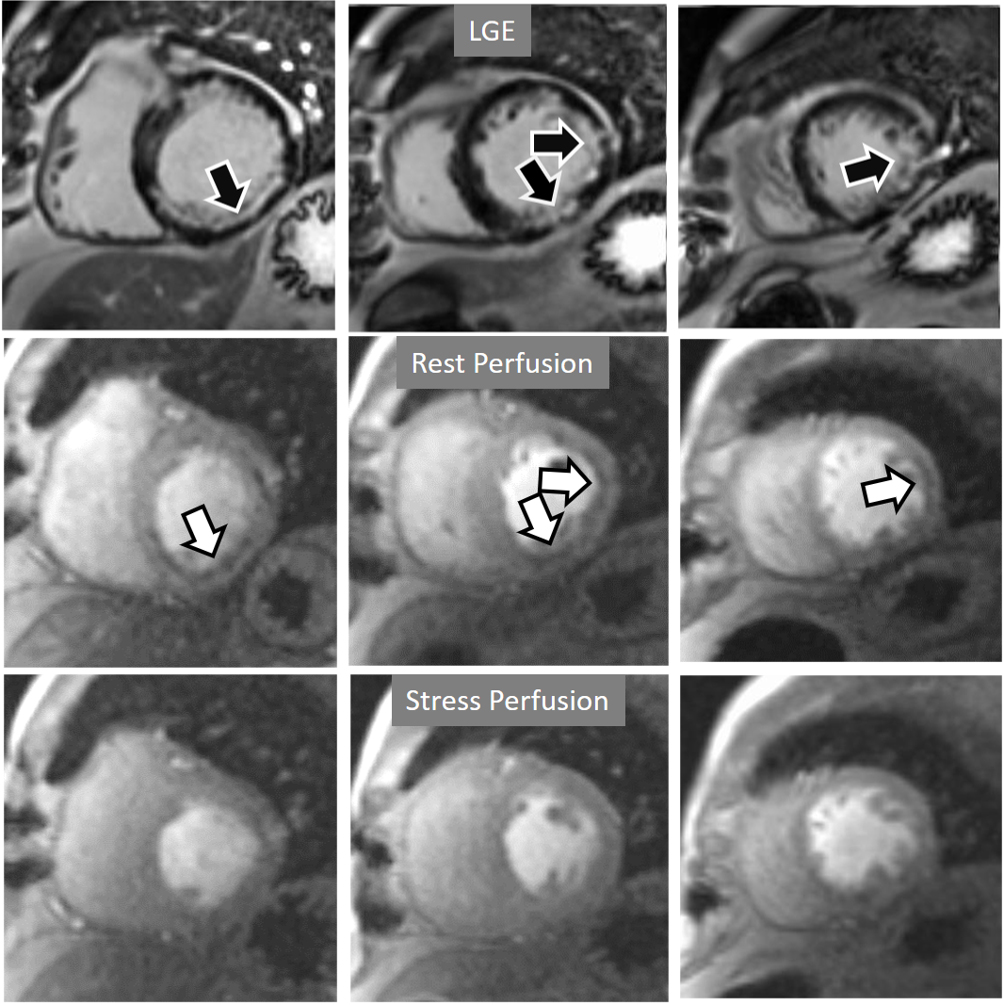

When considering both, the variability of rest perfusion in the presence of previous MI, and the rather low sensitivity of partially reversible defects, the interest in knowing the actual extension of fixed defects emerges. An option to address the issue is to invert the order of perfusion studies in patients with previous MI, performing the rest study first. This allows for a reliable delineation of the fixed defect that can be easily subtracted from the inducible one, when present (Fig. 18). Moreover, in the case of patients with advanced, severe CAD, in whom a combination of infarcted regions and underperfused territories can be expected, a basal rest perfusion study followed by the stress one is even more helpful (Fig. 19). Certainly, the presence of CA in an area of MI after the first rest perfusion study may contaminate the SI of the second one, but this does not preclude the detection, or exclusion, of newly induced defects (Fig. 20).

Fig. 20.Rest/Stress perfusion in chronic myocardial infarction. Subendocardial inferior and infero-lateral MI (black arrows, in the upper panel), leading to a comparable fixed defect at a basal rest study (white arrows, middle panel), and with no apparent defect under stress (lower panel). This latter finding is admittedly due to contamination of residual CA from the previous dose at the infarcted regions. This does not prevent, however, to rule out any newly induced defect.